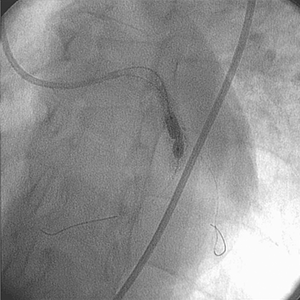

• El uso del sistema Rotablator™ facilitó el implante y la expansión adecuada de un stent de 4,0 mm × 9,0 mm con buen aspecto angiográfico.

Comentario del médico

El sistema Rotablator™ modificó la resistencia de la lesión y posteriormente facilitó el implante y la correcta expansión del stent mostrando con claridad su aplicación.

La evaluación angiográfica no reveló la presencia de calcio en la lesión.

Después de varios intentos por dilatar la lesión con balones, el nivel y la magnitud de la calcificación fue evidente. Si bien la oliva de 1,75 mm no aumentó el tamaño de la luz, sí permitió la posterior expansión de la lesión por medio de un balón y un stent para ACTP.